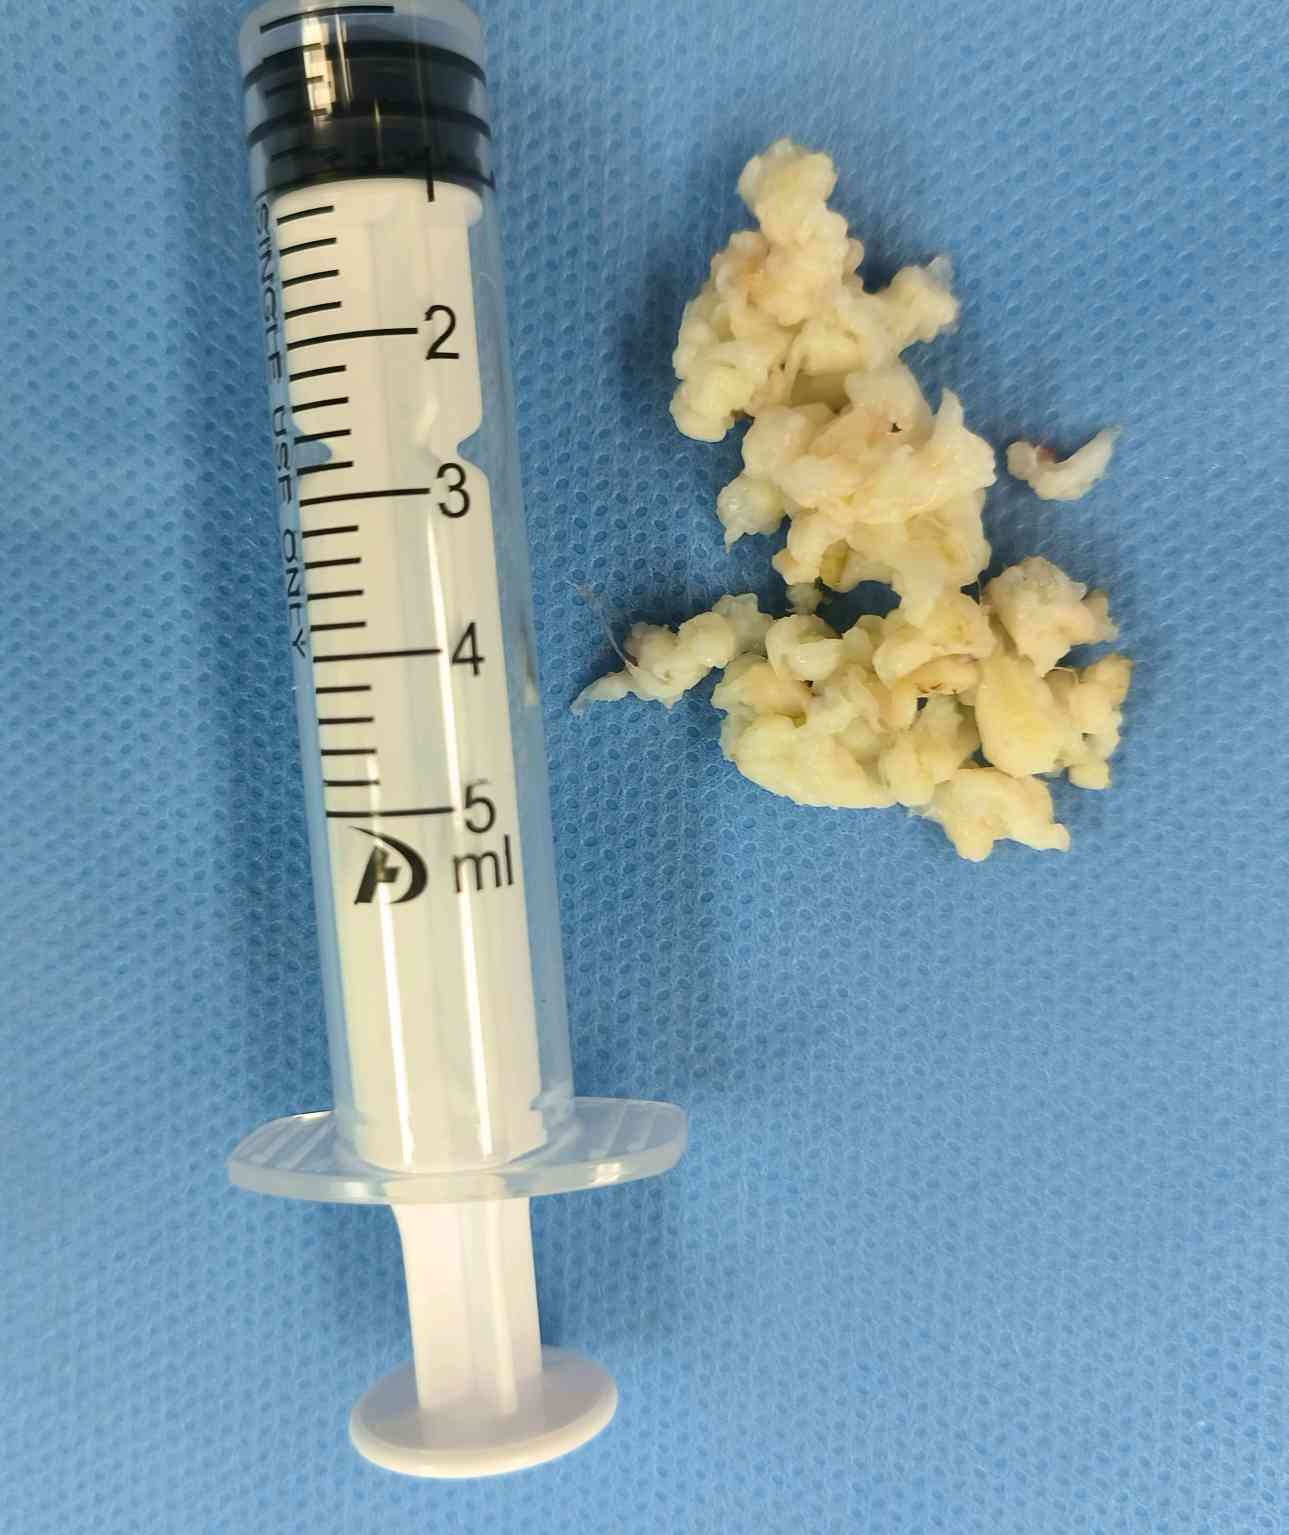

术中取出的压迫神经的髓核,这么大的髓核,靠针灸推拿,怎么可能会疼痛缓解?